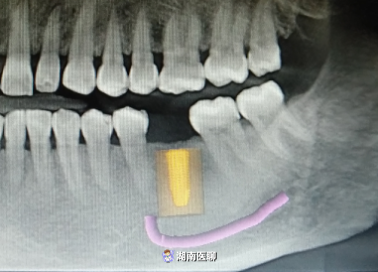

(種植術(shù)后cbct)

向峰醫(yī)生便為胡大姐“量身定制”了種植術(shù)前設(shè)計(jì)準(zhǔn)備。

(術(shù)前種植設(shè)計(jì))

術(shù)后,經(jīng)口腔CBCT檢查,植入的種植體的三維方向都十分契合。